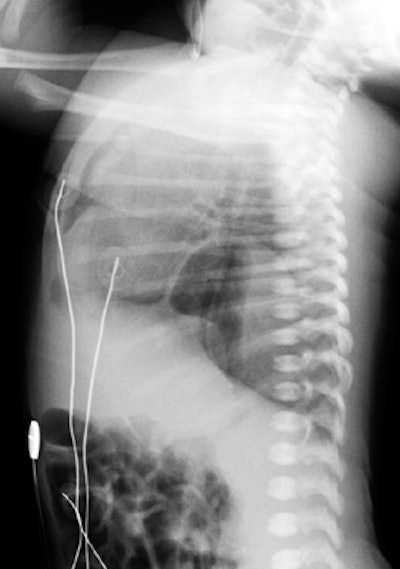

Unsuspected congenital diaphragmatic hernia: The newborn shown below presented with respiratory difficulty, but did not have a scaphoid abdomen. The frontal CXR demonstrated and abnormal lucency and curvilinear density in the left base. A lateral view revealed findings concerning for a diaphragmatic hernia. This was confirmed on CT imaging- note that a portion of the stomach and the spleen have herniated through the defect. |